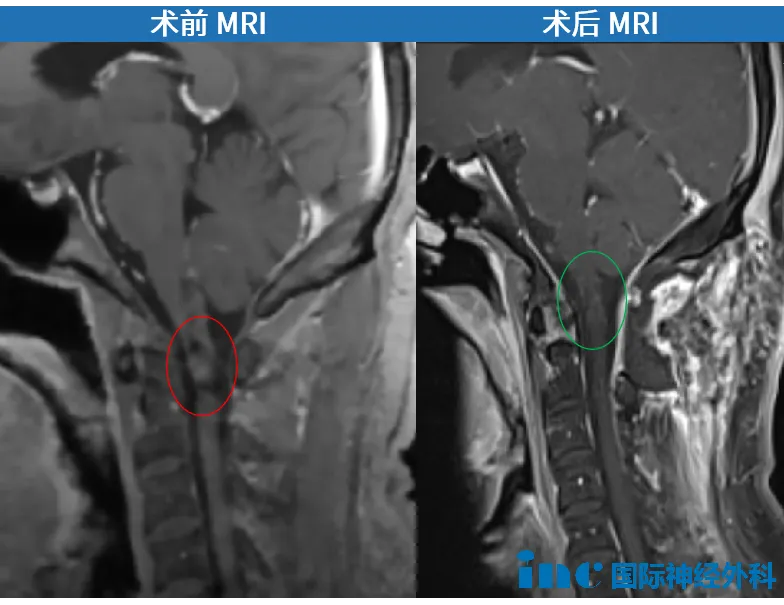

“影像显示了位于C1颈髓内的一个海绵状血管畸形此前导致了一次内生性出血,进而向上扩展到延髓下部。实际上,导致最初出血的根本原因是位于脊髓右侧的血管畸形。但手术切除技术上完全可行。我知道如何安全暴露病灶,虽然不是紧急手术,但结合你之前的出血情况,尽早切除才能避免后续风险。”

同时,教授也坦诚:“之前出血已损伤部分神经,术后症状可能不会完全消失,但会有改善。”

10月2日,手术正式开始。无影灯下,巴教授主刀,中国团队密切配合,每一步操作都小心翼翼。经过数小时的奋战,手术顺利完成。

术后第1天,郑先生就顺利转出ICU。术后部分功能也在好转。术后一年,郑先生早已回到正常生活,甚至能偶尔运动健身。